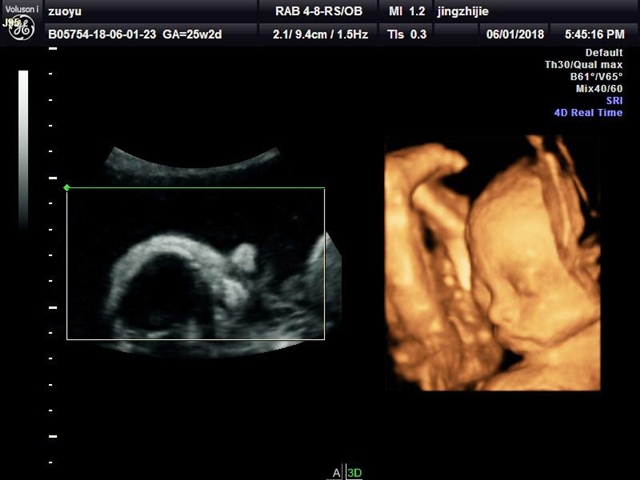

孕22周+3天

张嘴打哈欠那张萌到我了😄

叮噹猫[帖主]:哈哈……我们这边医院每次B超我们什么都看不到,我特意去的外面摄影工作室拍的四维,6个多月以来第一次见到宝宝的影像,打哈欠刚好拍成视频了,第一个六一节还纪念了一下